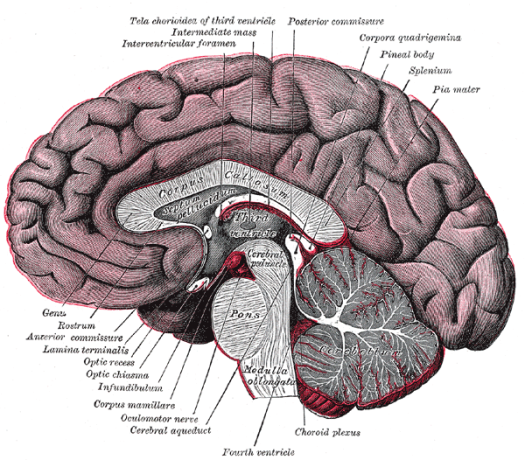

Figura 1: la glándula pituitaria ó hipófisis. Imagen recuperada de http://www.nlm.nih.gov/medlineplus/spanish/ency/esp_imagepages/17227.htm, el 17 de julio de 2007

Hoy, vamos a agregar un ingrediente más, en este peculiar programa de cocina cerebral, una estructura similar a un guisante (algunos científicos hablan del formato de pera muy pequeña ó de San Juan), con un peso de 0.5 gramos, que se denomina científicamente glándula pituitaria (también conocida como hipófisis, “crecimiento inferior”) y que se aloja en un espacio óseo, la silla turca, del hueso esfenoides, situada en la base del cráneo, en la fosa cerebral media, que conecta con el hipotálamo a través del tallo pituitario o tallo hipofisario. La etimología es sumamente curiosa para comprender anatómicamente esta microestructura de extraordinaria importancia en las mujeres y hombres, por este orden. Pituitaria significa que contiene o segrega pituita, del latín “pituita”: secreción, fluido, moco, flema, formando parte de la medicina tradicional junto a los tres “humores” restantes: sangre, bilis amarilla y bilis negra. Es una superestructura del sistema endocrino dado que ejerce un control férreo sobre ocho glándulas endocrinas que explicamos a continuación.

Esta glándula está unida al hipotálamo a través de fibras nerviosas y está formada por tres secciones: el lóbulo anterior, que representa el 80% del peso de la glándula, el lóbulo intermedio y el lóbulo posterior. El lóbulo anterior produce la hormona de crecimiento, la prolactina, que estimula la producción de leche materna después de dar a luz, la adrenocorticotrópica (ACTH), que estimula las glándulas adrenales, la estimulante de la tiroides (TSH), que estimula la glándula tiroides, la folículo-estimulante (FSH), que estimula los ovarios y los testículos al igual que la luteinizante (LH), también presente.

El lóbulo intermedio, produce la hormona estimulante de melanocitos que controla la pigmentación de la piel. El lóbulo posterior, produce la hormona antidiurética (ADH), que aumenta la absorción de agua en la sangre por medio de los riñones. Igualmente, la oxitocina, que contrae el útero durante el parto y estimula la producción de la leche materna.

Esta supercentral hormonal cumple unas funciones determinantes en el ser humano. Louann Brizendine, la autora revelación sobre el cerebro femenino, sitúa la glándula pituitaria como sexta estructura que lo caracteriza: “produce las hormonas de la fertilidad, producción de leche y comportamiento de crianza. Ayuda a poner en marcha el cerebro maternal”. Además, en el salto de la pubertad se desencadena la propulsión de las células hipotalámicas y la niña-mujer comienza a experimentar cambios que ya se repetirán día a día, mes a mes hasta la menopausia, porque “la glándula pituitaria… salta a la vida cuando los frenos químicos se sueltan en las células hipotalámicas […]. Esta liberación celular dispara el sistema hipotalámico-pituitario-ovárico” (1). El conocimiento de esta realidad recurrente en la vida de la mujer debe ayudar a los hombres a respetar íntegramente estos ciclos vitales que producen desajustes vitales, por responsabilidad directa de la naturaleza al estar muy desarrollada esta glándula en la mujer en el lóbulo anterior de la misma (recuerdo que el peso específico de esta zona desarrolla el 80% de su función diaria y perfectamente programada). No ocurre lo mismo en el cerebro masculino, porque el balanceo hormonal no pasa tanta factura en la vida ordinaria. Si se conoce bien esta estructura, se respeta. Además, se pueden poner ejemplos rotundos de este “conocimiento” cerebral femenino, basados en una hormona bastante desconocida a nivel popular pero que juega un papel trascendental en la mujer y en las relaciones de pareja. Me refiero a la oxitocina, una hormona muy atractiva para el objeto de estas publicaciones.